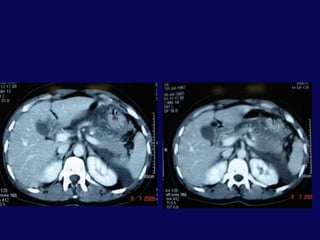

Hasta işlem sonrası 23. gününde ateş, bulantı, kusma şikayetleriyle yeniden yatırıldı.BT’ de karaciğer ve mide arasında 6x5 cm’lik bir koleksiyon tespit edildi. Perkütan drenaj uygulandı. 200 cc geleni oldu.

Hastanın ilk konan dreninden geleni olmaması üzerine çekildi. Yeni drenden 150 cc geldi. Hasta işlem sonrası 3. gününde kontrole gelmek üzere taburcu edildi. 3. hafta kontrolde debi olmaması üzerine dren çekildi